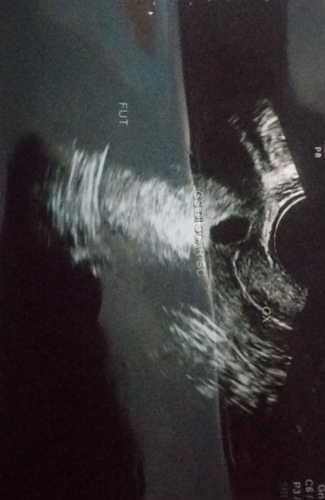

Contoh hamil di luar kandungan. Hamil di luar kandungan atau ektopik termasuk kasus yang jarang namun moms tetap perlu mengetahui apa saja hal hal yang bisa jadi penyebab masalah ini. Hamil di luar kandungan atau disebut juga dengan kehamilan ektopik berpotensi mengancam nyawa jika tidak segera ditangani. Definisi apa itu kehamilan ektopik hamil di luar kandungan. Hamil di luar kandungan dalam bahasa medis sering disebut juga dengan kehamilan ektopik merupakan sebuah kehamilan yang terjadi ketika sel telur yang telah dibuahi oleh sel sperma menempel di bagian lain selain rahim. Dilansir dari laman ectopic dalam beberapa kondisi langka sel telur bisa menempel di tempat lain seperti ovarium di serviks. Kehamilan tersebut seringkali terjadi dibagian tuba falopi.